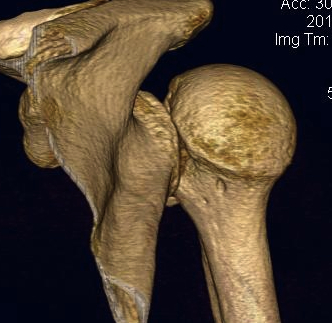

CT scan

Confirms dislocation

Reverse Hill Sachs

Humeral head defect

- caused by impaction of anterior humeral head on posterior glenoid

- intra-articular

- measured as a percentage of the articular surface

Lesser tuberosity fractures

Posterior glenoid fractures / bony bankart